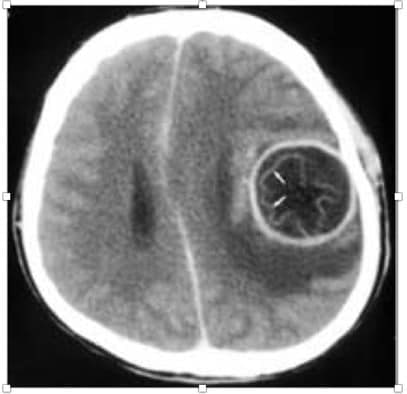

کیست هیداتید مغزی و بررسی موارد درمان شده در مرکز آموزش درمانی شهید مطهری ارومیه از سال 1369 تا 1379

بعد از چند هفته، این تخم ها در بافت های مختلف میزبان واسط مخصوصا در کبد، ریه، طحال، مغز و استخوان، به کیست هیداتید تبدیل می شود که در افراد آلوده با برخی عوارض همراه است. از نظر اپیدمیولوژی ارتباط نزدیک با سگ ها به عنوان میزبان انگل، می تواند در پراکندگی بیماری کیست هیداتید موثر باشد. هدف این مطالعه بررسی موارد مغزی جراحی شده در مدت 10 سال می باشد.

در این مطالعه توصیفی گذشته نگر 500 مورد توده فضاگیر تحت درمان جراحی قرار گرفته از نظر جنس، سن، محل کیست در مغز، محل زندگی بیمار منفرد و متعدد بودن آنها مورد تجزیه و تحلیل قرار گرفتند.

یافته ها: از 500 توده ی مغزی تحت عمل جراحی قرار گرفته در بخش جراحی مغز 16 مورد (%3.2) مبتلا به کیست هیداتید مغزی بودند. از این 16 مورد، 9 نفر، زیر 15 سال سن داشتند، 7 مورد بالای 15 سال سن داشتند.

از لحاظ جنسی 10 نفر %62.5 مونث و 6 نفر (%37.5) مذکر بودند. در 14 مورد (%87.5) کیست ها در قسمت بالای تنتوریوم(قسمت فوقانی مغز) و در 2 مورد (%12.5) در قسمت پایین تنتوریوم قرار گرفته بودند.

در %12.5 موارد کیست های متعدد ولی در اکثر موارد %87.5 افراد کیست منفرد داشتند.

در تصویر برداری، سی تی اسکن و ام آر آی هر دو مفید است.